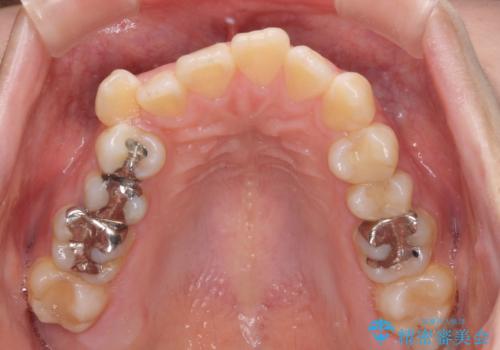

- 八重歯と口の閉じにくさを気にして来院された患者様です。

上下ともに前歯が前方に突出し、八重歯が唇に引っかかる感じもあり、口が閉じにくくなっていました。

上下左右の第一小臼歯4本を抜歯し、口元の突出感を改善しながら八重歯を解消していくこととしました。